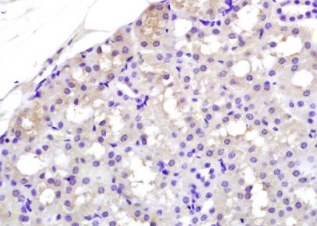

组织/细胞:大鼠肾组织;4%多聚甲醛固定石蜡包埋;

抗原提取:柠檬酸缓冲液(0.01M,pH 6),15min煮沸,用3%过氧化氢阻断内源性过氧化物酶30min;37℃下阻断缓冲液(正常山羊血清)20 min;

孵育:抗APAF1(NT)多克隆抗体,未结合1:200,在4°C下过夜,然后与二级抗体结合,DAB染色。